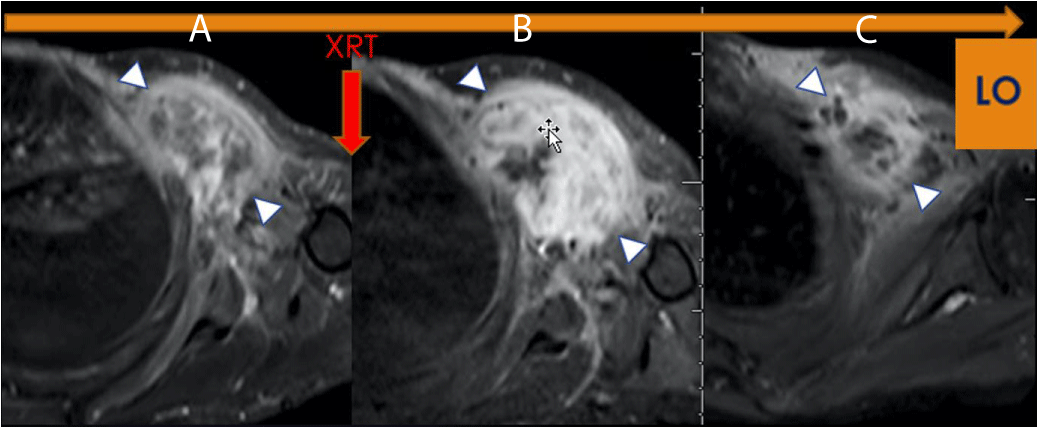

From our experience, pseudo-progression is commonly observed in Good Responders. It may demonstrate a volume increase of up to 60% at Post Chemotherapy and 90% at Post-Radiation, both in the range of disease progression by RECIST, even in patients with the most significant response, with more than 90% of treatment-induced necrosis (TIN) (Figure 1).

Figure 1: LO (Learning Objective): Pseudo progression due to Radiation Therapy. Axial FS T1 post-contrast imaging of the left shoulder demonstrates (A) a Pre-therapeutic tumor, (B) an increase in the size and enhancement of the tumor, (C) Without additional therapy, there has been a decrease in size and enhancement indicating pseudoprogression on Figure 1b (arrowhead). The histologic specimen demonstrated 95% necrosis, combined with granulation tissue and no viable tumor.